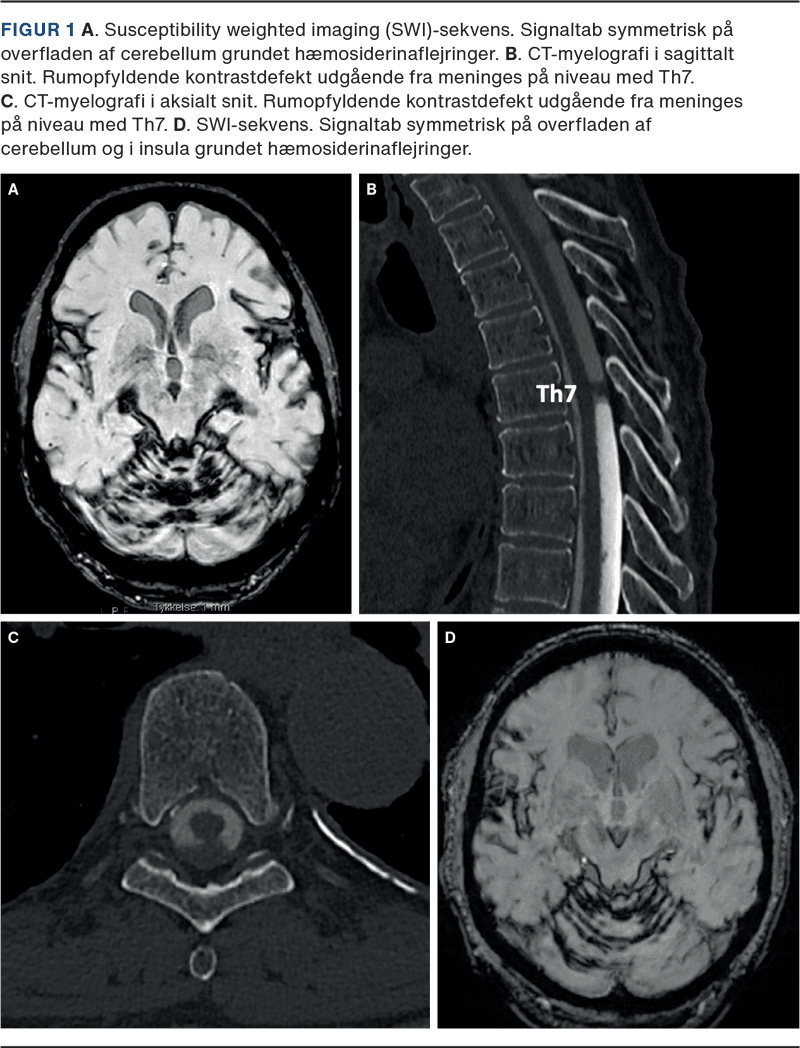

I 2017 blev han henvist til neurolog på grund af nedsat balance, men han blev ikke yderligere udredt. Patienten blev genhenvist i 2019 med langsomt progredierende gangbesvær, følelsesløshed i begge ben og progredierende høretab. Der blev fundet ataktisk gang. Der var normal neurofysiologisk undersøgelse. MR-skanning af cerebrum viste jernaflejring over cerebellum på susceptibilitetsvægtede sekvenser (Figur 1A).

MR-skanning af medulla spinalis blev beskrevet med pial siderosis, men uden nogen påvist blødningskilde, og man gik videre med CT-myelografi, der viste udfyldning i dura mater spinalis ved Th7 (Figur 1B og C).

Patienten blev i 2022 initialt undersøgt i øre-næse-hals (ØNH)-regi på grund af progredierende høretab over de seneste tre år. Patienten fik høreapparater, og ØNH-afdelingen foranledigede MR-skanning af cerebrum, som viste iSS med jernaflejring infratentorielt (Figur 1D).